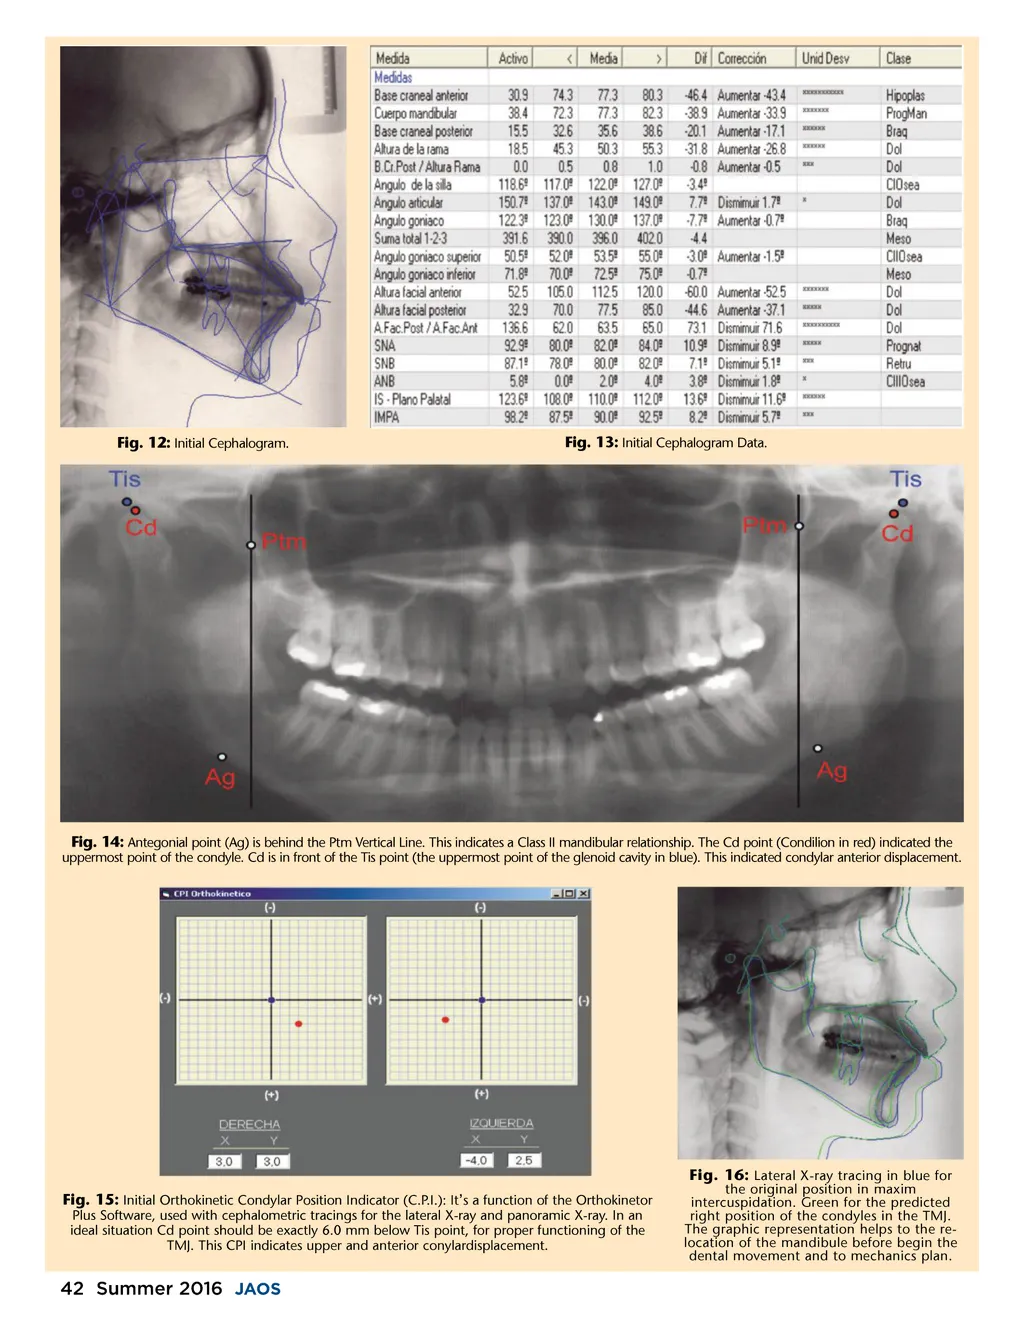

Fig. 12: Initial Cephalogram. Fig. 13: Initial Cephalogram Data. Fig. 14: Antegonial point (Ag) is behind the Ptm Vertical Line. This indicates a Class II mandibular relationship. The Cd point (Condilion in red) indicated the uppermost point of the condyle. Cd is in front of the Tis point (the uppermost point of the glenoid cavity in blue). This indicated condylar anterior displacement. Fig. 15: Initial Orthokinetic Condylar Position Indicator (C.P.I.): It ’ s a function of the Orthokinetor Plus Software, used with cephalometric tracings for the lateral X-ray and panoramic X-ray. In an ideal situation Cd point should be exactly 6.0 mm below Tis point, for proper functioning of the TMJ. This CPI indicates upper and anterior conylardisplacement. the original position in maxim intercuspidation. Green for the predicted right position of the condyles in the TMJ. The graphic representation helps to the re-location of the mandibule before begin the dental movement and to mechanics plan. Fig. 16: Lateral X-ray tracing in blue for 42 Summer 2016 JAOS